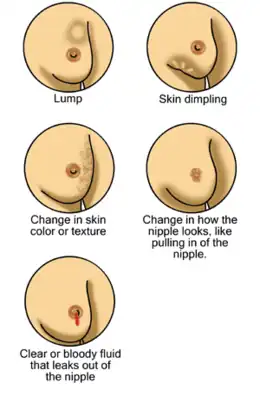

| Symptoms | A lump in a breast, a change in breast shape, dimpling of the skin, fluid from the nipple, a newly inverted nipple, a red scaly patch of skin on the breast[1] |

Breast cancer is a cancer that develops from breast tissue.[7] Signs of breast cancer may include a lump in the breast, a change in breast shape, dimpling of the skin, milk rejection, fluid coming from the nipple, a newly inverted nipple, or a red or scaly patch of skin.[1] In those with distant spread of the disease, there may be bone pain, swollen lymph nodes, shortness of breath, or yellow skin.[8]

Most people with breast cancer have no symptoms at the time of diagnosis; their tumor is detected by a breast cancer screening test.[19] Those who do have symptosm commonly feel a lump that feels different from the rest of the breast tissue. Lumps found in lymph nodes located in the armpits[20] may also indicate breast cancer. Indications of breast cancer other than a lump may include thickening different from the other breast tissue, one breast becoming larger or lower, a nipple changing position or shape or becoming inverted, skin puckering or dimpling, a rash on or around a nipple, discharge from nipple/s, constant pain in part of the breast or armpit and swelling beneath the armpit or around the collarbone.[21] Pain ("mastodynia") is an unreliable tool in determining the presence or absence of breast cancer, but may be indicative of other breast health issues.[20][22][23]

Another symptom complex of breast cancer is Paget's disease of the breast. This syndrome presents as skin changes resembling eczema; such as redness, discoloration or mild flaking of the nipple skin. As Paget's disease of the breast advances, symptoms may include tingling, itching, increased sensitivity, burning, and pain. There may also be discharge from the nipple. Approximately half the women diagnosed with Paget's disease of the breast also have a lump in the breast.[24][25]